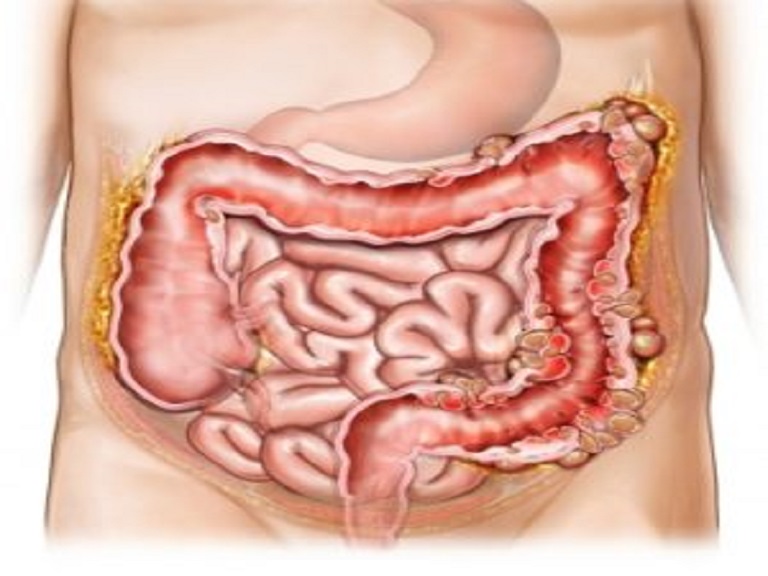

In Ayurvedic treatment Amlapitta is a disorder of the gastrointestinal tract (Annavaha Strotas) and can be correlated with modern-day Gastroesophageal Reflux Disease (GERD). The prevalence of GERD has increased significantly in recent years due to unhealthy food habits, irregular lifestyle patterns, and high-stress levels. Amlapitta is observed across all age groups, including children, adults, and the older people as well.

Amlapitta is primarily a disorder of the stomach (Amashaya Udbhav) and requires a multi-dimensional treatment approach involving detoxification, herbal medicine, and lifestyle modifications.